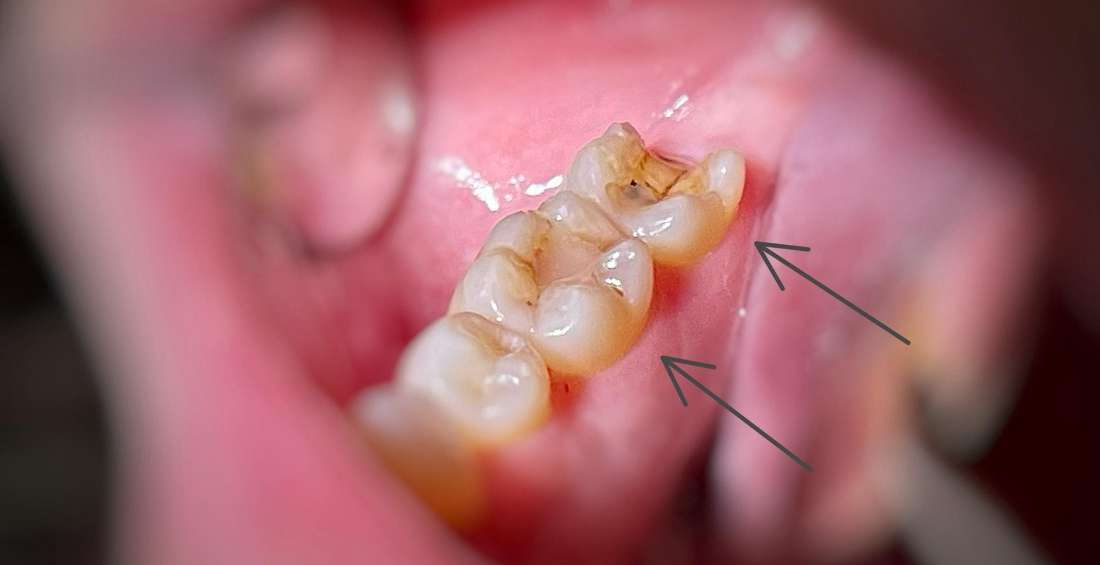

This patient came to our dental office in South Charlotte. One tooth lost most of its chewing surface and was cracked. We were able to save the tooth with a CEREC same day crown. Another tooth nearby had an old filling that was starting to break down. We restored this tooth with a composite white filling.